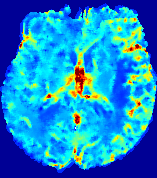

4.3.2 Diffusion Imaging via Advection-Diffusion

Slice #1Slice #2Slice #3Slice #4Slice #5Slice #6Dgtsuperscript𝐷gtD^{\text{gt}}Refer to captionRefer to captionRefer to captionRefer to captionRefer to captionRefer to captionDestsuperscript𝐷estD^{\text{est}}Refer to captionRefer to captionRefer to captionRefer to captionRefer to captionRefer to captionRefer to caption0.300.300.300.240.240.240.180.180.180.120.120.120.060.060.060.000.000.00(mm2/s)𝑚superscript𝑚2𝑠(mm^{2}/s)𝐕est𝟐subscriptnormsuperscript𝐕est2\|\bf{V}^{\text{est}}\|_{2}Refer to captionRefer to captionRefer to captionRefer to captionRefer to captionRefer to captionRefer to caption0.00300.00300.00300.00240.00240.00240.00180.00180.00180.00120.00120.00120.00060.00060.00060.00000.00000.0000(mm/s)𝑚𝑚𝑠(mm/s)

Figure 15: PIANO identifiability testing: diffusion imaging via advection-diffusion. Top row shows Dgtsuperscript𝐷gtD^{\text{gt}} used for simulating ground truth pure diffusion. Rows below show the estimated Destsuperscript𝐷estD^{\text{est}} and 𝐕est2subscriptnormsuperscript𝐕est2\|{\bf{V}}^{\text{est}}\|_{2} on corresponding slices. Note that the plotted value scale for 𝐕est2subscriptnormsuperscript𝐕est2\|{\bf{V}}^{\text{est}}\|_{2} is 0.01 of that for Dgtsuperscript𝐷gtD^{\text{gt}} and Destsuperscript𝐷estD^{\text{est}}.

Similarly, we test the behavior of PIANO when estimating both advection and diffusion from a pure diffusion-driven process. The goal is to determine if PIANO is able to recognize that there is only diffusion governing the given concentration time-series. We use the same ‘Diffusion Imaging’ data simulation of Sec. 4.2.1 as the concentration dataset, PIANO estimates both velocity 𝐕estsuperscript𝐕est{\bf{V}}^{\text{est}} and diffusivity Destsuperscript𝐷estD^{\text{est}}. Estimation results in Fig. 15 confirm PIANO’s identifiability again: the estimated 𝐕est2subscriptnormsuperscript𝐕est2\|{\bf{V}}^{\text{est}}\|_{2} is almost invisible compared to Destsuperscript𝐷estD^{\text{est}}, even plotted with a 1%percent11\% value range compared to that for Destsuperscript𝐷estD^{\text{est}}. On the other hand, Destsuperscript𝐷estD^{\text{est}} achieves comparable estimation performance as ‘Diffusion Imaging via Diffusion’ in which PIANO predicts Destsuperscript𝐷estD^{\text{est}} alone (shown in Fig. 13).